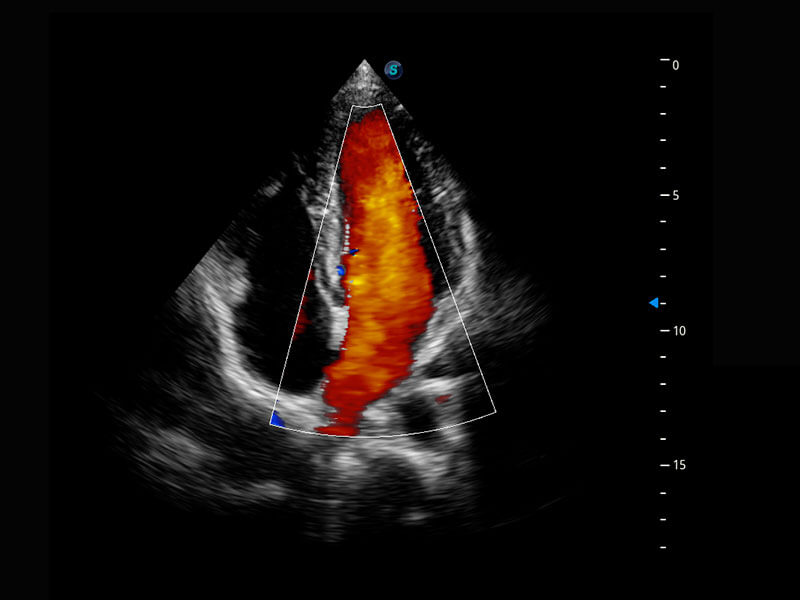

P60搭载一系列胎儿心脏成像技术,实现精细的胎儿心脏评估。

四腔切面

四腔心血流